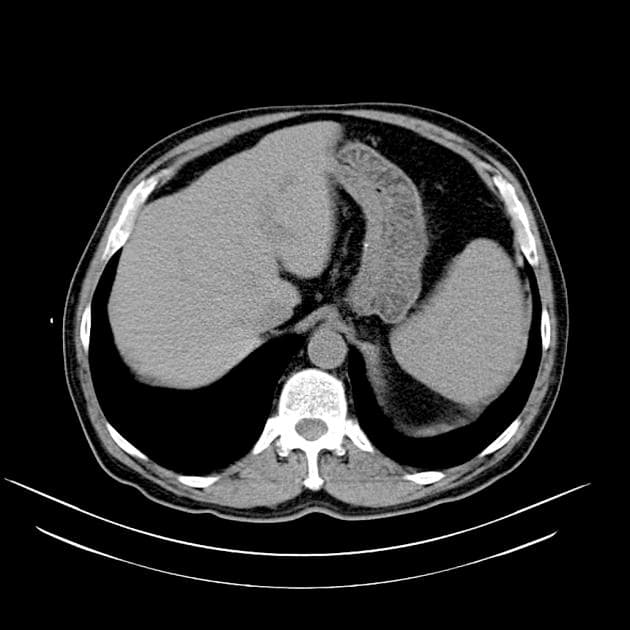

Axial C+ delayed

- Ghi nhận khối tổn thương bán lồi ra ngoài (exophytic), dị tỷ trọng (hetero-dense), kích thước 133 × 114 × 122 mm, ở mặt trước thận trái. Sau tiêm thuốc cản quang, khối cho thấy ngấm thuốc không đồng nhất (heterogeneous enhancement) với vùng hoại tử trung tâm (central necrosis) rộng lớn. Không có dấu hiệu xâm lấn tại chỗ và không có lan rộng vào mạch máu.

- Ghi nhận nang đơn thuần thành mỏng, không ngấm thuốc (non-enhanced), kích thước 20 mm ở thuỳ gan trái.